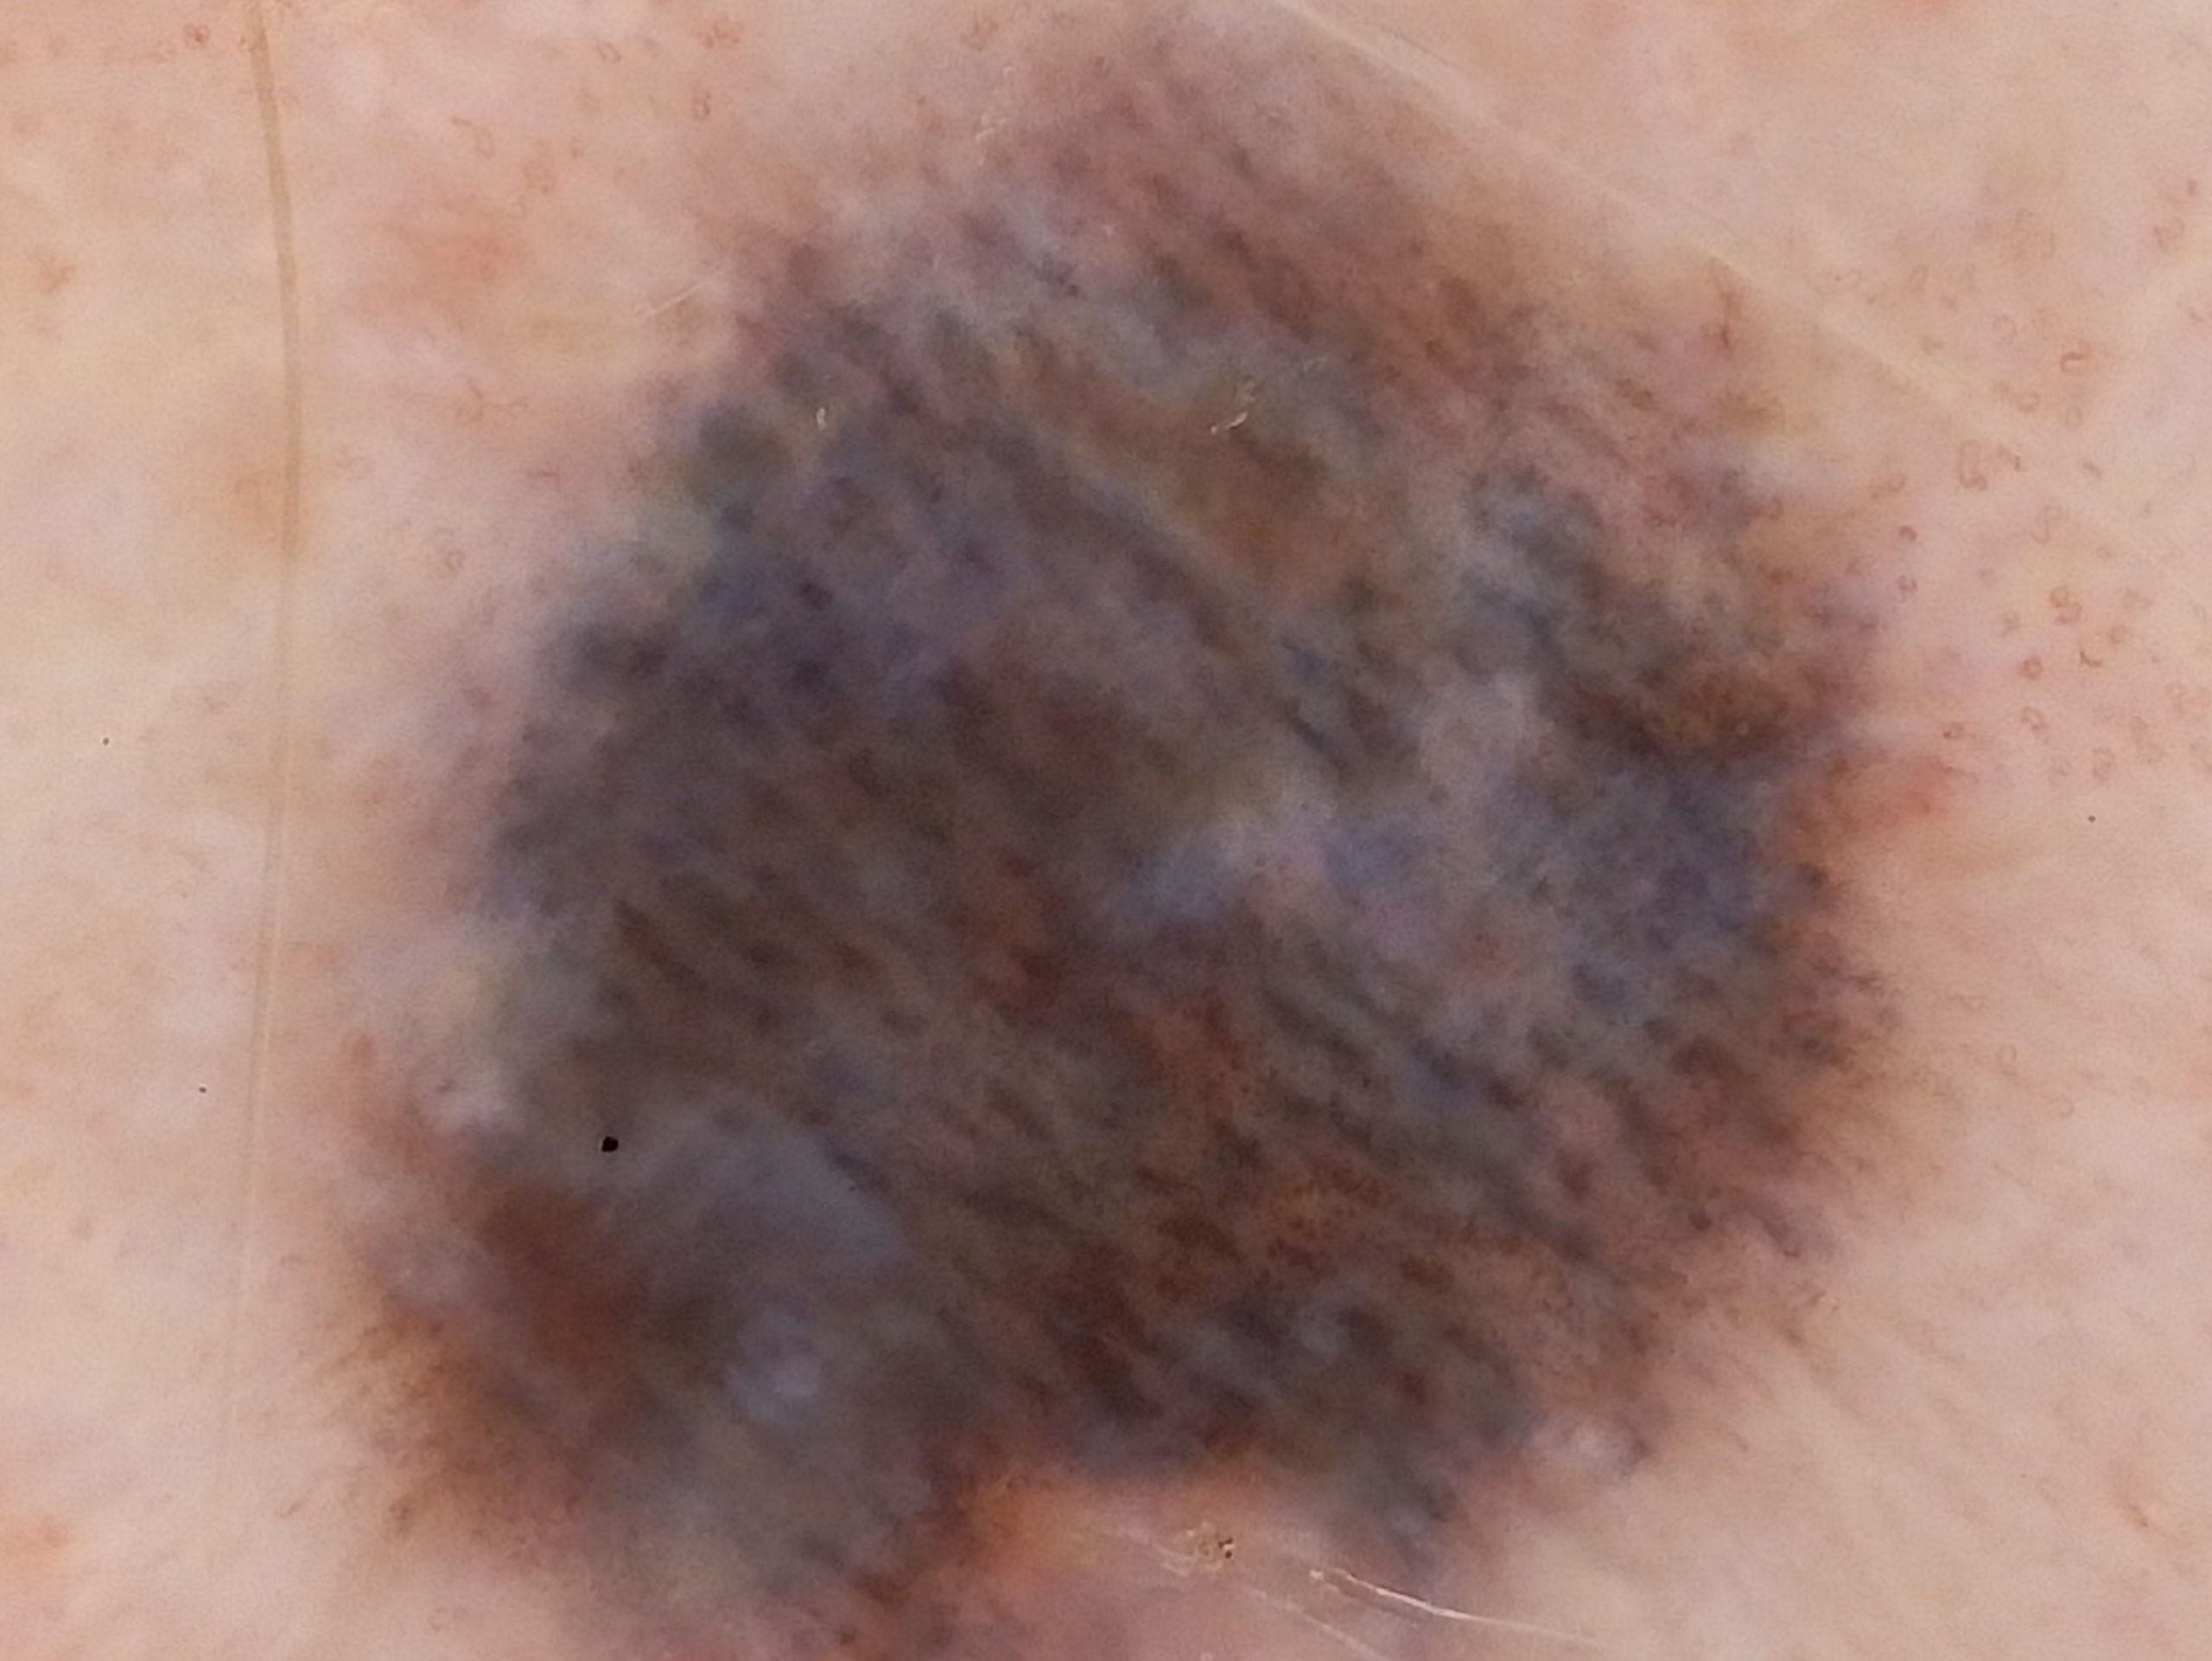

Site: Ankle

Diagnosis: Post Inflammatory Hyperpigmentation

Description: Note the perilesional hypopigmentation

These lesions arose after he went on Check Point inhibitor for metastatic melanoma. Note the perilesional hypopigmentation as well as the post inflammatory hyperpigmentation which was all that was left of his melanoma metastases. These had been stable for the last 9 months with no evidence in PET scans of melanoma elsewhere. This rteally shows the effectiveness of these immune stimulating drugs in metastatic melanoma.